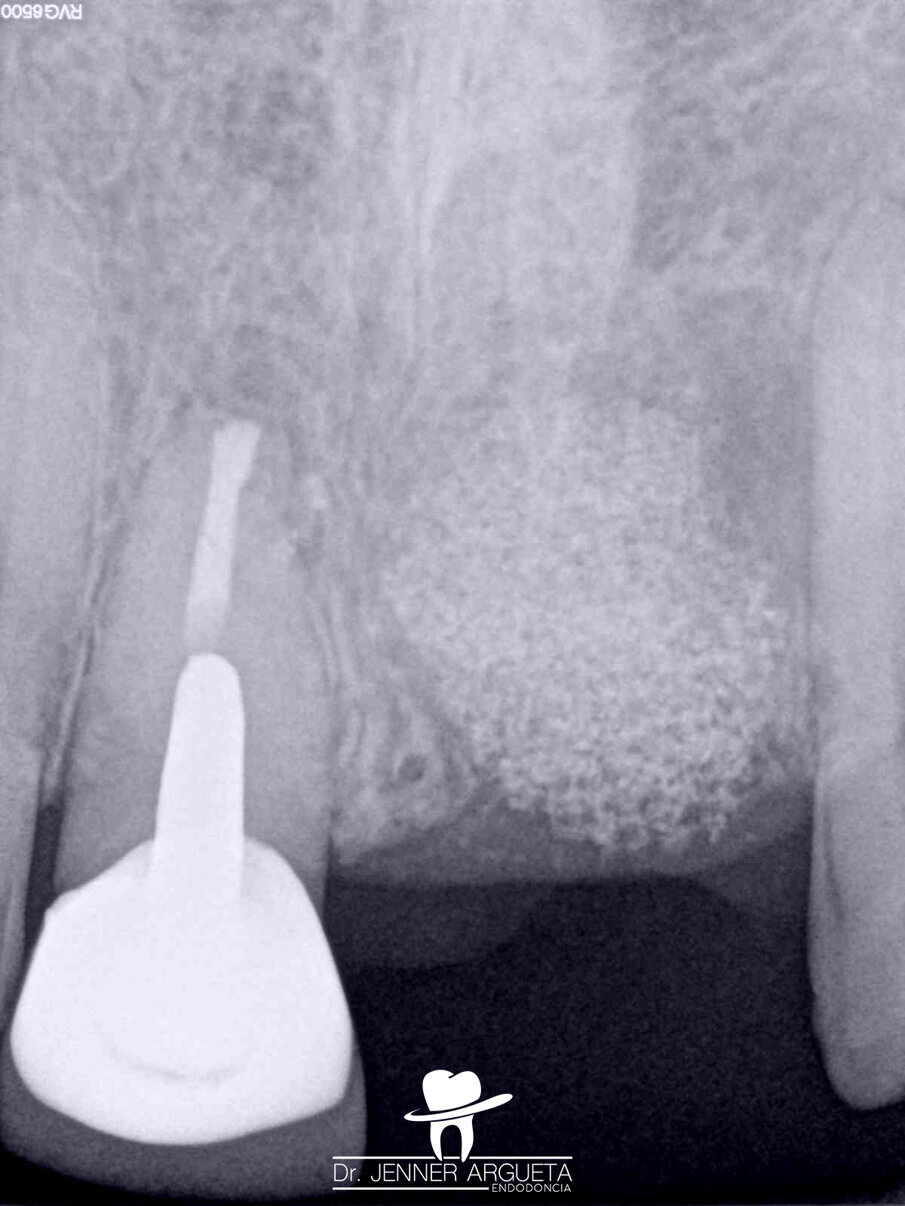

A 35-year-old male patient reported pain affecting the central incisors. Upon clinical examination, an acute periapical abscess was detected; radiographically, resorptive radicular defects in tooth #11 were observed. The patient reported a traumatic injury in the area several years before. The established diagnosis was pulp necrosis and an acute periapical abscess.

Figs. 6a–c: Radiographic sequence of the treatment performed in tooth #11. Initial radiograph. The root resorption and lateral radiolucent area were evident (a). Working length measurement at the level of the resorption (b). Root resorption repair with a calcium silicate-based material (c).

Figs. 7a–c: Radiographic sequence of the treatment performed in tooth #11. Initial radiograph. The root resorption and lateral radiolucent area were evident (a). Master cone fitting at the level of the complete working length (b). Completed root canal therapy (c).

Fig. 8: Radiographic sequence of the treatment performed in tooth #11. Initial radiograph. The root resorption and lateral radiolucent area were evident (a). Completed root canal therapy (b). Three-year follow-up radiograph showing complete healing of the lateral radicular radiolucent area and the correct sealing of the resorption (c).

During the first appointment for root canal therapy, it was not possible to reach the complete length of the root canal, because the files tended to go inside of the mesial resorption. It was decided to seal the resorptive defect (Fig. 6a–c) using CeraSeal sonically activated using the EQ-S device (Meta Biomed; see video below).

At the second appointment, the material placed at the resorption was completely hard. That hard barrier allowed the file to pass through the entire length of the physiological root canal. The root canal therapy was finished using CeraSeal as the endodontic sealer (Fig. 7a–c). The three-year follow-up radiograph showed complete healing of the lateral radicular radiolucent area (Fig. 8a–c).